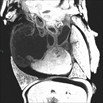

Caption: Small right ventricle (RV) and hypoplastic pulmonary trunk in mutant 913-005-NA (details)